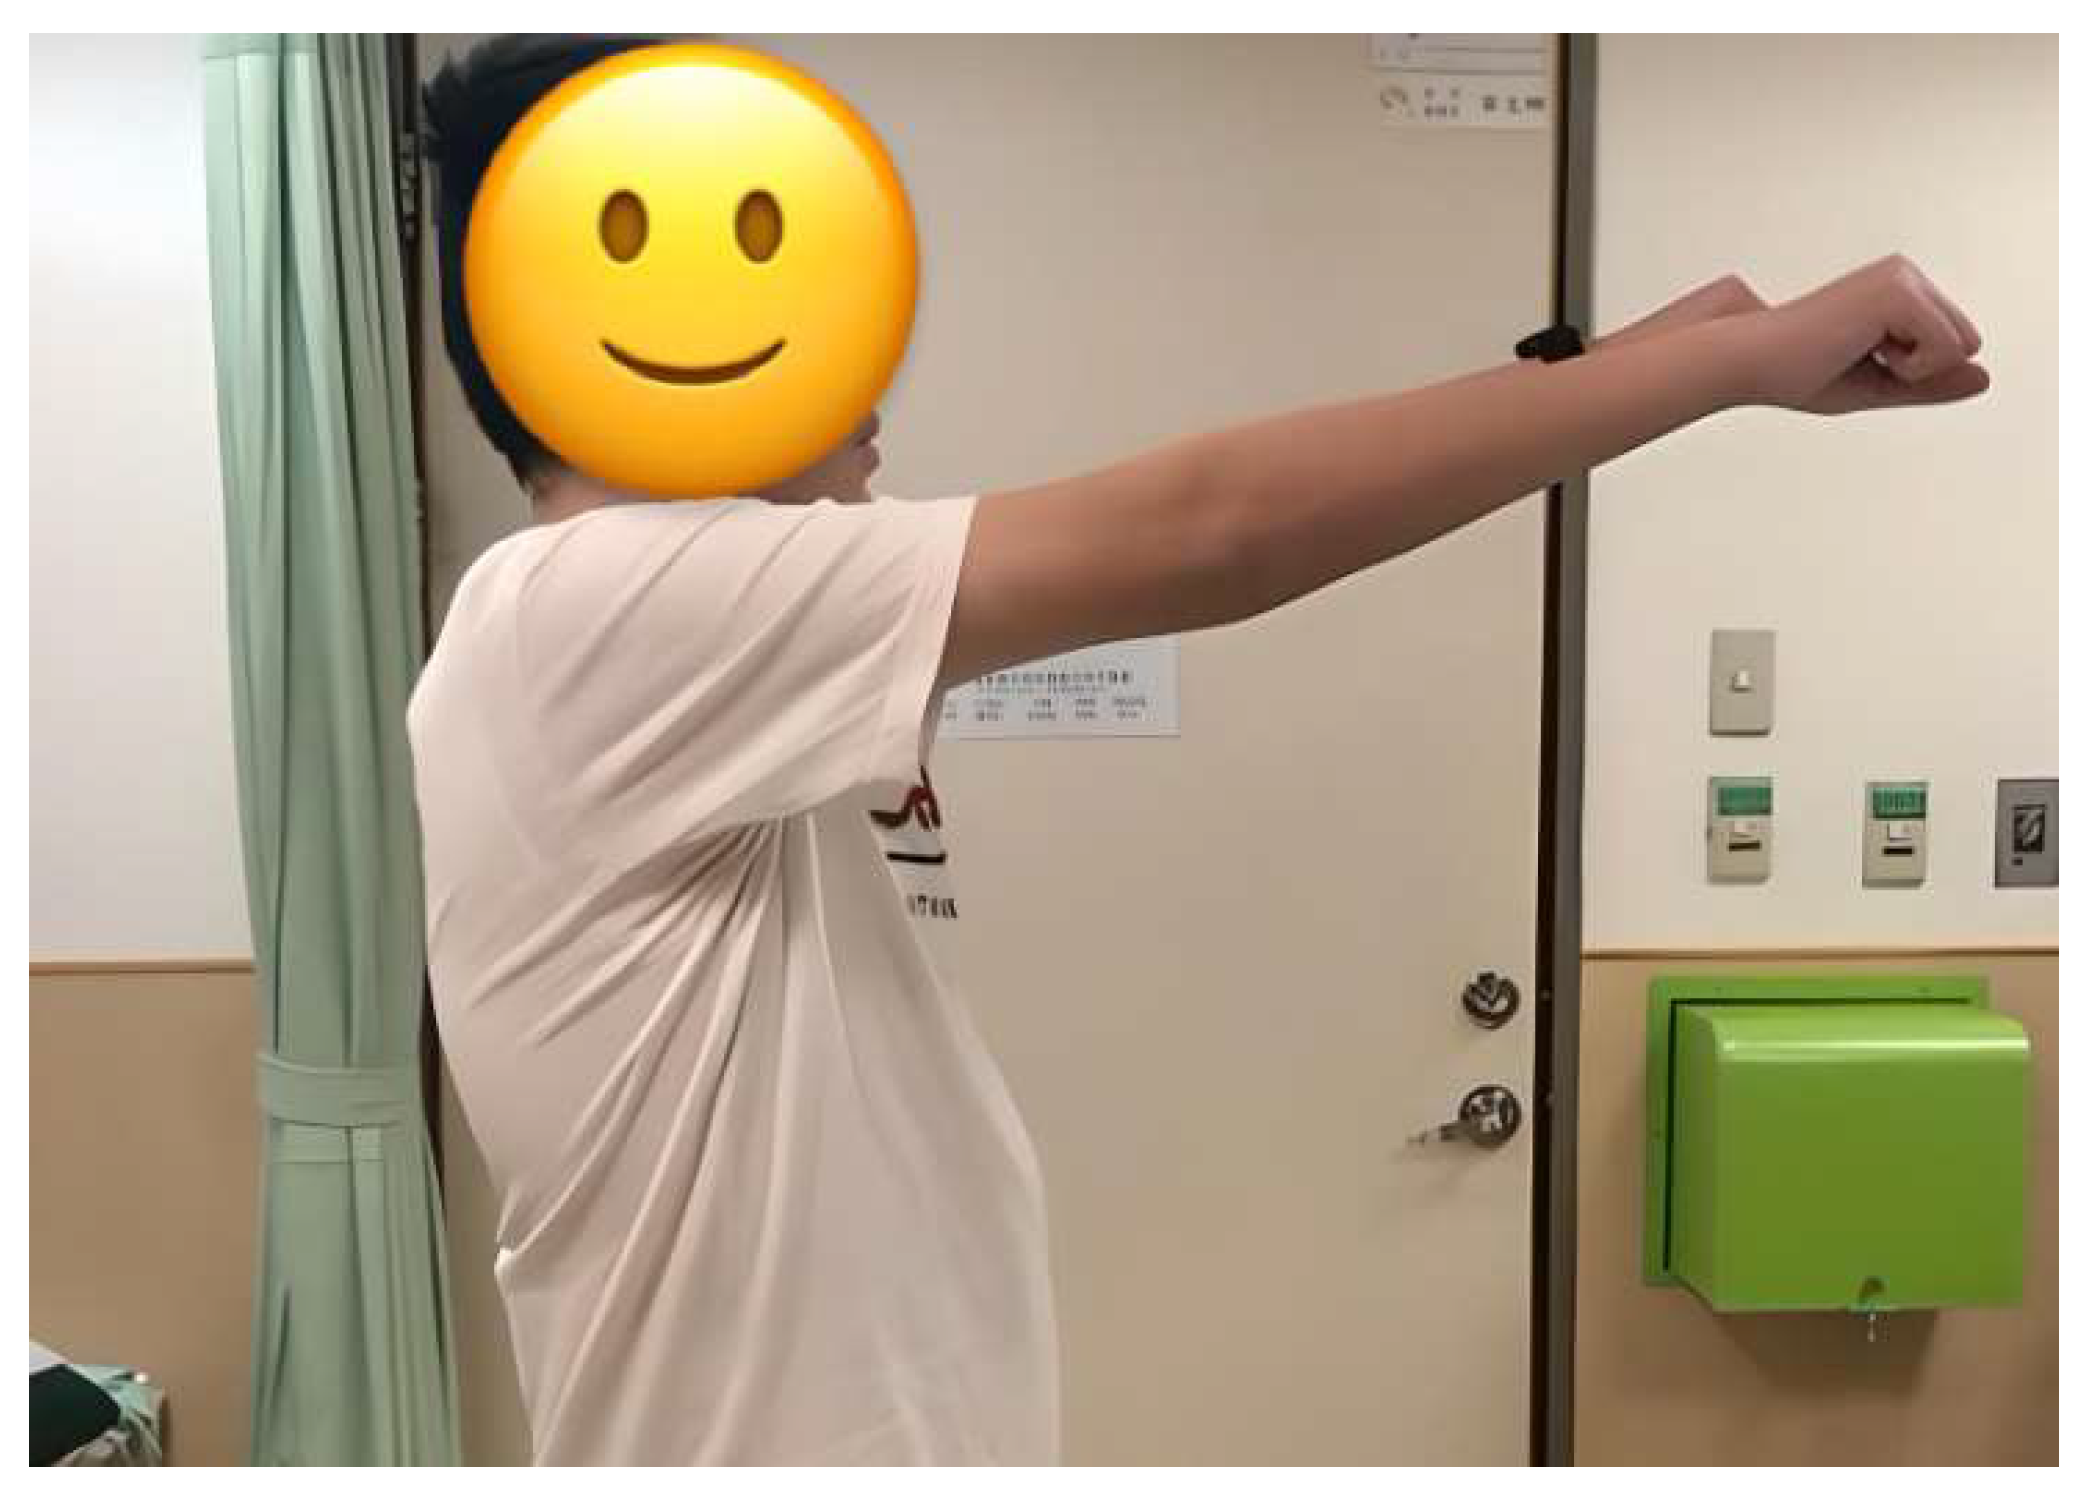

2.4. Surgical Procedure and Postoperative Care